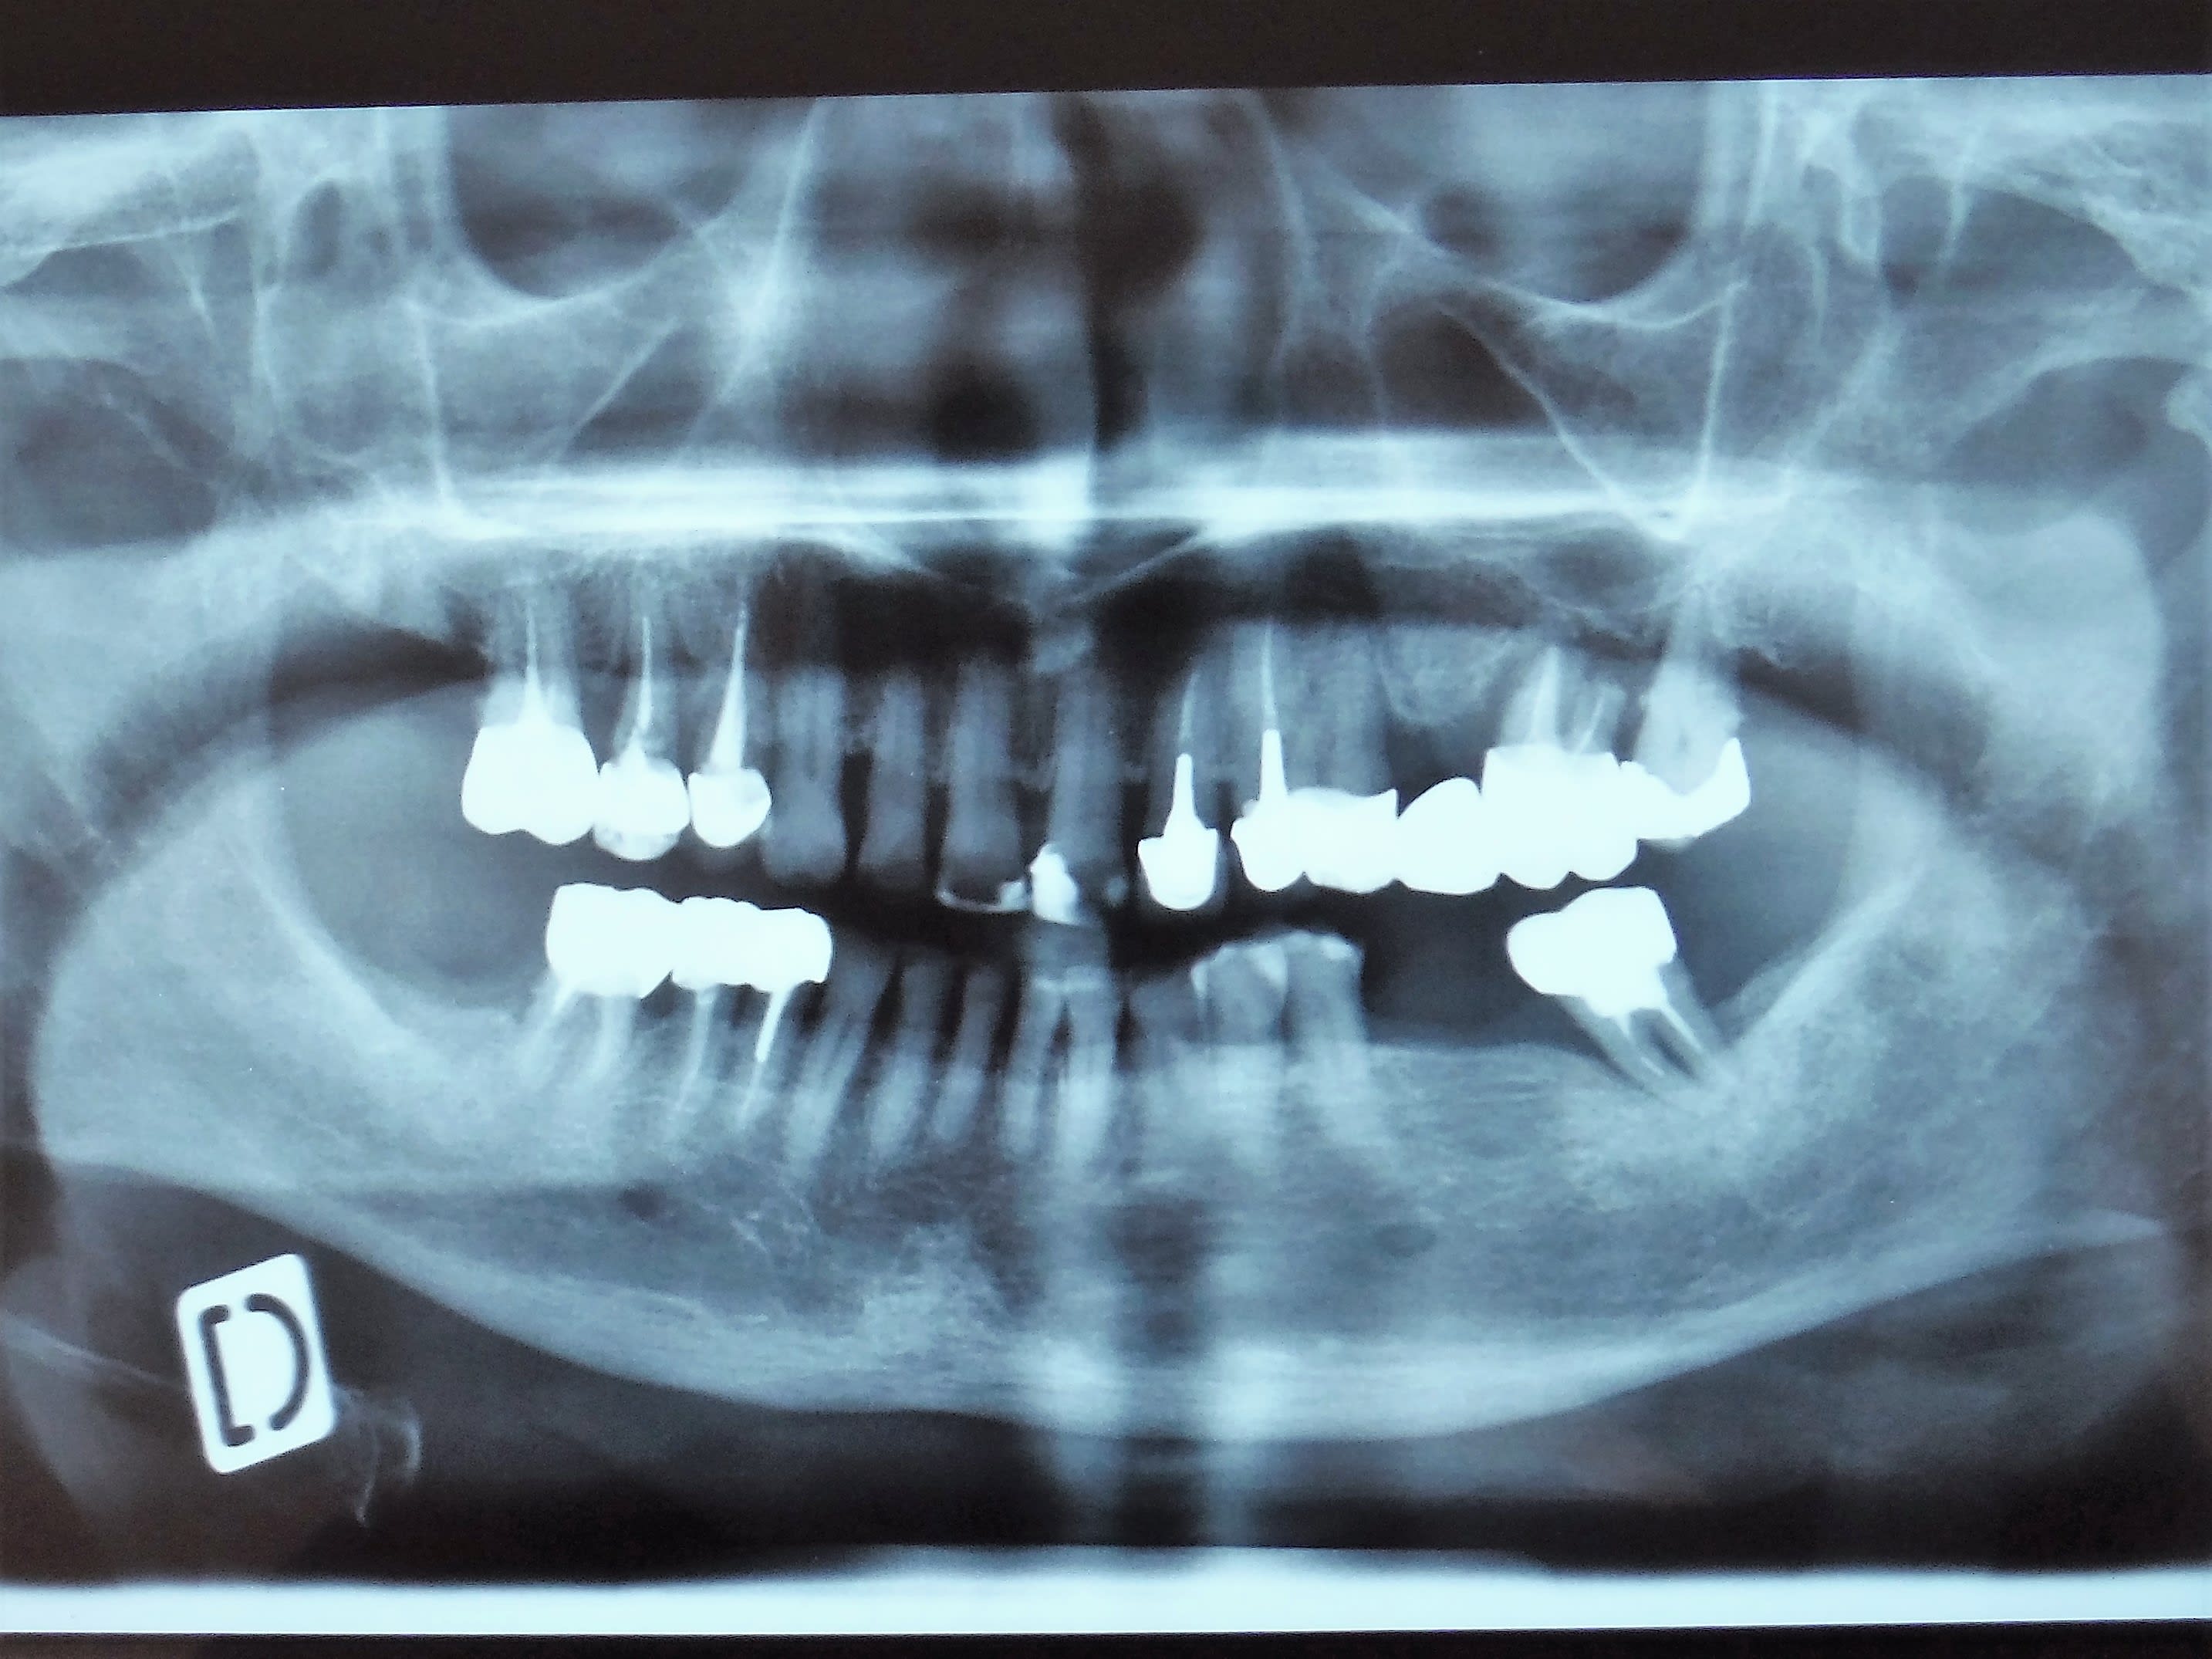

ben écoute elle a vu un dentiste ailleurs qui lui a dit " c'est les dents de sagesse ".

Moi au départ je me suis dit " Oui c'est ça cause toujours tu m'intéresses , faut arrêter la fumette ma grande " 😊 mais effectivement elle a 3 molaires de chaque coté au maxillaire dont une qui est pas tout à fait sur l'arcade ... ce qu'on voit c'est la 2eme molaire plus derrière la 3eme molaire

y aurait pas un truc au niveau des centrales?-)

Oups l'endo de 16 c'est bibi... généreux le vulpi;-)

c'est la fameuse dent qu'on dénomme ectopique... ou y a un autre nom pour la denomer je crois . M'en rappelle plus